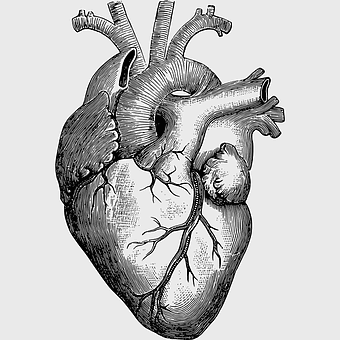

human heart diagram, monochrome anatomy drawing, black and white heart illustration, human organ sketch, cardiovascular system diagram, medical illustration heart, heart structure outline -

human heart anatomy, cardiovascular system illustration, medical heart diagram, heart organ structure, human body organ visuals, anatomical heart drawing, heart health -

human heart anatomy, superior vena cava illustration, systemic circulation diagram, heart rate visual, cardiovascular system study, medical organ depiction, human body organ reference -

Heart Anatomy Diagram, human heart drawing, realistic heart illustration, cardiovascular system, medical illustration, organ structure, human anatomy study -